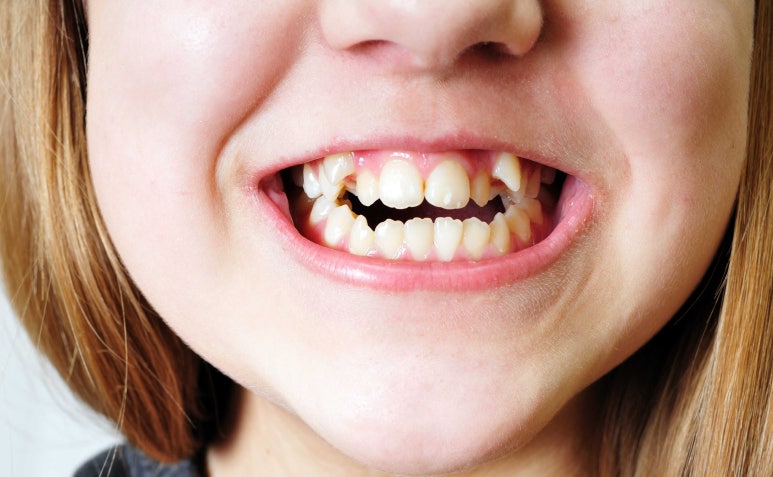

치아 한두개가 유난히 툭 튀어나와있는 #덧니 로 인해 스트레스 받는 분들 참 많으실겁니다.

덧니는 귀여운 이미지를 주기도 하지만, 반대로 가지런하지 못하다, 깔끔하지 못하다는 인상을 주기도 하니까요.

덧니는 치아가 맹출해야 할 공간의 부족으로 약간 비뚤어져 나거나, 덧대어져 나는 치아를 의미합니다.

이런 특성상 전체적인 치아의 배열이 어긋나보이기도 하고, 가지런하지 못하게 되죠.

자, 먼저 이번 사례 환자분의 라미네이트 치료 전 사진을 먼저 보여드리겠습니다.

환자분은 다른 치아들은 비교적 가지런한 편인데 왼쪽 3번째 송곳니 (사진상 오른쪽)

#23 치아가 다소 뻐드러져있는 상태였습니다.